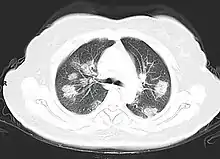

التصوير

تشمل السمات المميزة في تصوير الصدر الشعاعي والمقطعي المحوسب للأشخاص العرضيين عتامات زجاج مغشى محيطية غير متناظرة دون انصبابات جنبية.[122] تجمع جمعية الأشعة الإيطالية قاعدة بيانات دولية على الإنترنت لنتائج تصوير الحالات المؤكدة.[123] نظرًا للتداخل مع العداوى الأخرى مثل عدوى الفيروس الغداني، يعد التصوير دون التأكيد بواسطة آر تي-بي سي آر الفوري ذو نوعية محدودة في الكشف عن كوفيد-19.[122] قارنت دراسة كبيرة في الصين نتائج التصوير المقطعي المحوسب للصدر بالبي سي آر وأشارت إلى أنه على الرغم من أن التصوير أقل كشفًا للعدوى، لكنه أسرع وأكثر حساسية.[124]